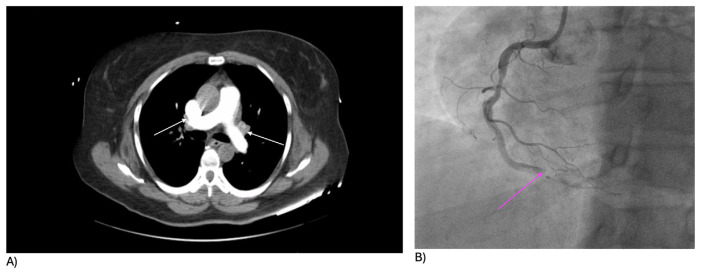

安非他明的使用与心血管风险的增加有关,如肺动脉高压、心律失常和动脉粥样硬化。一位47岁的女性在服用减肥药芬特明后发生了次心梗。她表现为胸痛、呼吸短促和呕吐。初步检查显示血压低,心率慢。随后的检查显示心脏酶水平升高,心电图显示ST段升高。冠状动脉造影显示右冠状动脉阻塞。她成功地接受了打开动脉的手术。该病例强调了与使用安非他明相关的心血管风险增加,即使在没有心脏疾病的个体中也是如此。研究和临床指南对于更好地预测、诊断和管理此类并发症至关重要。

Amphetamine use is associated with increasing rates of cardiovascular risks, such as pulmonary hypertension, arrhythmias, and atherosclerosis. A 47-year-old woman experienced an inferior MI after taking the weight loss drug phentermine. She presented with chest pain, shortness of breath, and vomiting. Initial examination showed low blood pressure and slow heart rate. Subsequent tests revealed elevated cardiac enzyme levels and ST elevations on EKG. A coronary angiogram showed a blockage in the right coronary artery. She underwent a successful procedure to open the artery. The case highlights the heightened cardiovascular risks associated with amphetamine use, even in individuals without existing heart conditions. Research and clinical guidelines are crucial for better prediction, diagnosis, and management of such complications.